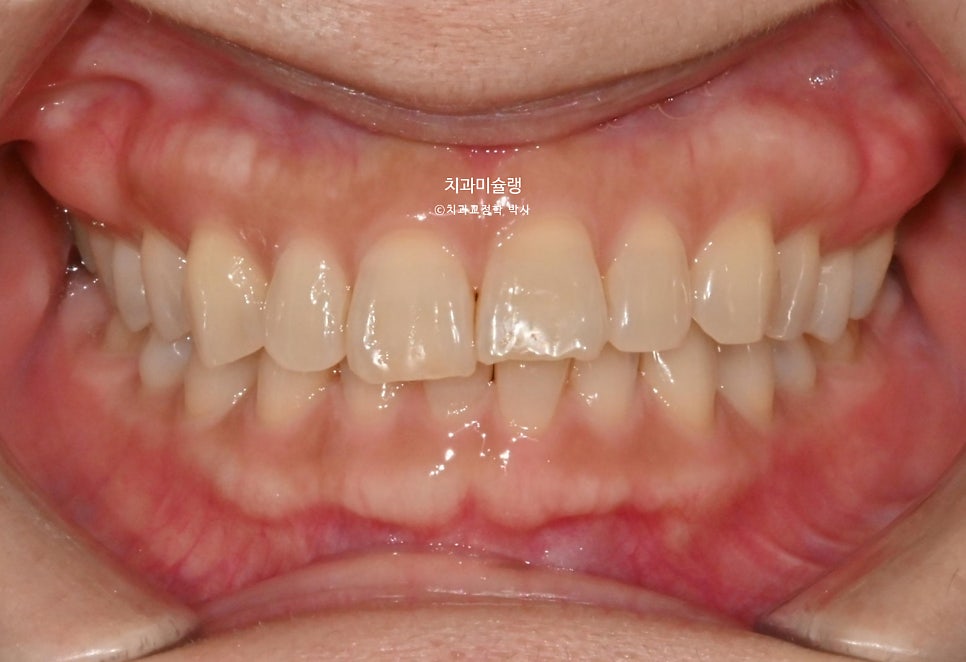

초진 시 구강 상태 분석

환자기준 우측 치아들이 내려와 있습니다. 앞니가 깊게 물리는 과개교합 입니다. 중심선 불일치도 보입니다.

웃을때 우측 치아들이 내려와 스마일라인이 기울어져 보입니다. (캔팅 이라고 합니다)

이렇게 치아가 기울어져 있는 캔팅이 있으면, 비대칭이 심해보입니다. 교정으로 캔팅이 개선되면 비대칭도 완화되어 보이죠.

어금니 교합은 좋은편.

앞니가 삐뚤합니다.